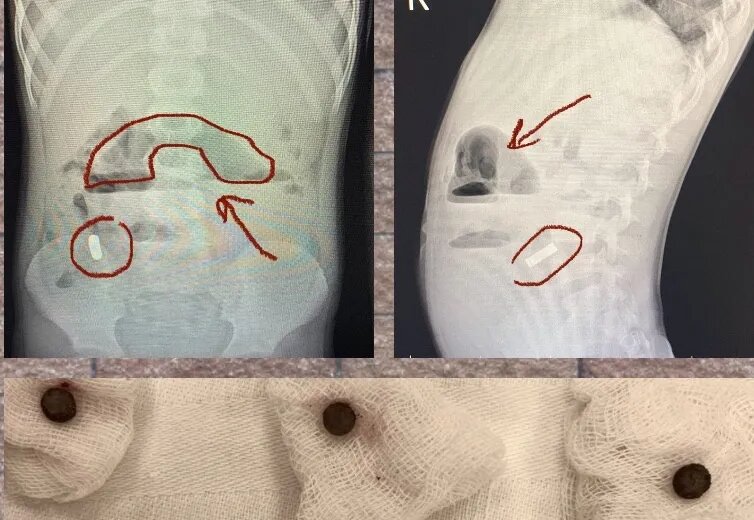

Хирурги ОДКБ №2 провели успешную операцию по извлечению инородных тел из кишечника маленького мальчика. Сейчас ребенок переведен в общую палату. Некоторое время назад 6-летний мальчик начала жаловаться на боли в животе. Уже на первичном приеме у мальчика обнаружили серьезные проблемы и госпитализировали. «Общий анализ крови и мочи был в пределах нормы, а живот болел на 10 из 10,- далее мы провели УЗИ органов брюшной полости, на котором и заподозрили наличие инородных тел», - рассказал хирург Владимир Кораблев. Как оказалось, в кишечнике мальчика скопилось 10 магнитов. Их ребенок проглотил не за раз. Инородные тела некоторое время находились на разных уровнях, но позже притянулись друг к другу, спровоцировав острую непроходимость кишечника. В итоге врачи провели операцию и успешно извлекли магниты. В данный момент мальчик чувствует себя хорошо, за его состоянием врачи наблюдают в общей палате. Не пропустить важное в ДЗЕН 36ON

Как оказалось, в кишечнике мальчика скопилось 10 магнитов. Их ребенок проглотил не за раз. Инородные тела некоторое время находились на разных уровнях, но позже притянулись друг к другу, спровоцировав острую непроходимость кишечника. В итоге врачи провели операцию и успешно извлекли магниты. В данный момент мальчик чувствует себя хорошо, за его состоянием врачи наблюдают в общей палате. Не пропустить важное в ДЗЕН 36ON